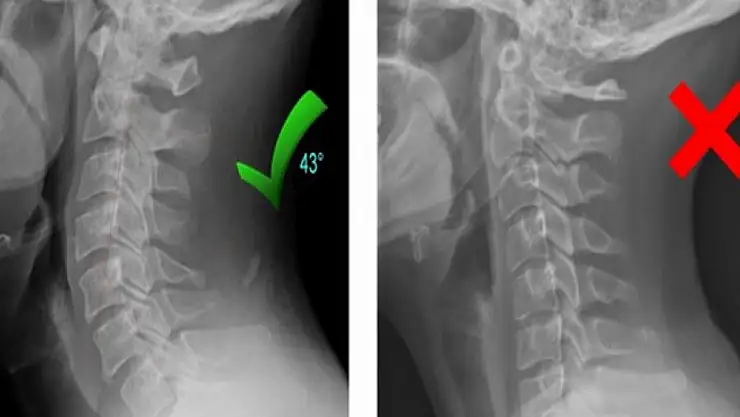

Özel Medicana Konya Hastanesi Fizik Tedavi ve Rehabilitasyon Uzmanı Dr. Öğr. Üyesi Sinan Bağçacı, boyun düzleşmesi ve boyun fıtığı hakkında bilgiler verdi. Boyun omurgasına binen yük karşılanamadığı zaman boyunda, disk ve diğer dokularda zedelenme ortaya çıktığını anlatan Dr. Öğr. Üyesi Sinan Bağçacı, "Boyun omurgasında normalde ön tarafa doğru olması gereken "C" harfi şeklindeki kıvrımın tamamen düz hale gelmesi ve hatta çok ilerler ise ters C gibi olması durumunda boyun düzleşmesinden bahsediyoruz. Bu durum uzun süre devam ettiği zaman boyun fıtığı ve kireçlenme ile kendini gösterebilir. Boyun düzleşmesinde ana neden boyun postüral bozukluğudur. Uzun süre devam eden boyundaki mekanik yüklenme ve postür bozukluğu boyun fıtığı kireçlenmesi ile sonuçlanır. Bel omurgasından sonra boyun vücudun en hareketli omurga segmentidir. Omurga boyun bölgesinde kafanın ağırlığını taşımakla birlikte, baş ve boyunda birçok eklemden oluşan yapı; hareketlerin sağlanması ve baş kontrolünü sağlamaktadır. Bu hareketlerin sağlanması ve boyuna binen yüke karşı konulabilmesi için omurlar arasındaki diskler görev almaktadır. Diskler omurlar arasına uygulanan kuvvetin emilerek dağıtılmasını sağlar. Omurgaya esnek bir yapı verir ve bundan dolayı zedelenmesine engel olur. Yaş ilerledikçe disklerin içerisindeki su miktarında azalma olur. Genç kişilerde disklerine anormal yük binmesi, yaşlı kişilerde ise zamanla disklerinde dejenere olması sonucunda disk içeriğinin fıtıklaşması ile sonuçlanan boyun fıtığı görülebilmektedir. Boyun fıtığı omurilik ve sinirlere baskı uygulayabilir" dedi.